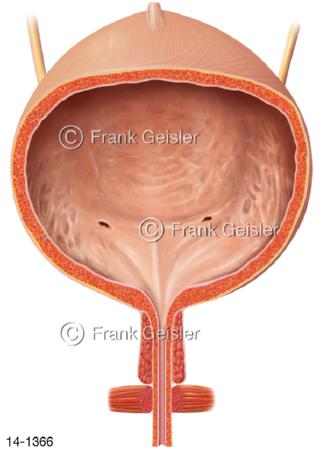

Bildergalerie Urogenitalsystem

Bilder zum Urogenitalsystem mit Urogenitalorgane, Urogenitaltrakt, zum Harn- und Geschlechtsapparat, Harnorgane und Geschlechtsorgane, Organe der Harnwege und der Fortpflanzung, Harnorgane und Geschlechtsorgane im männlichen und weiblichen Urogenitalsystem